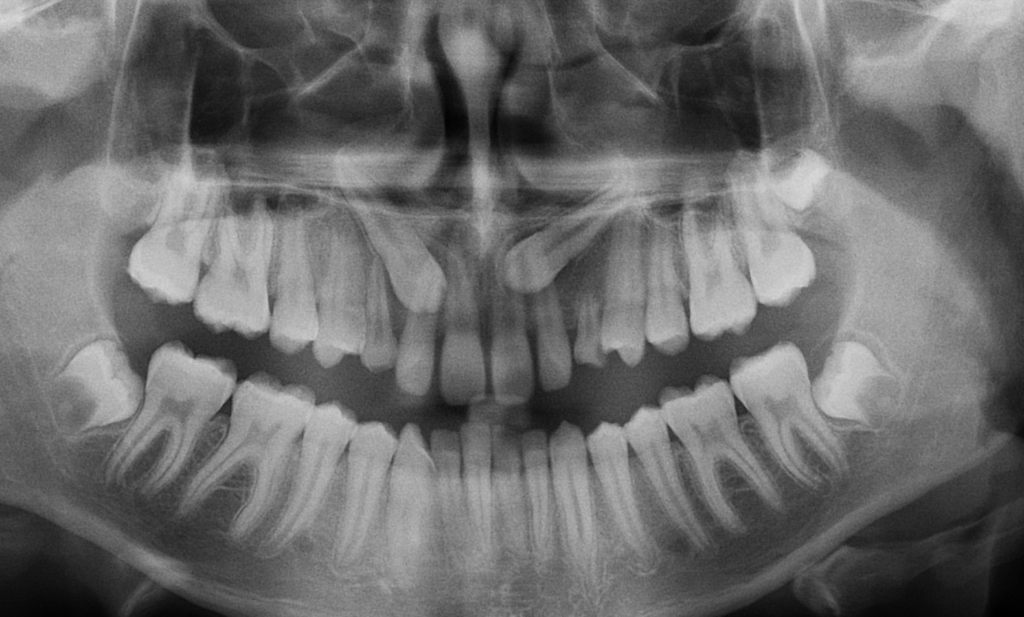

While wisdom teeth are the most commonly impacted teeth, canines are the second most common teeth to become impacted. When this happens, the tooth does not erupt into the mouth properly and instead remains trapped in the bone or gum.

An impacted canine occurs when the permanent canine tooth fails to erupt into the correct position in the mouth.

Instead of coming into place normally, the tooth may:

- Remain trapped under the gum or bone

- Erupt in the wrong location

- Push against nearby teeth

- Become stuck in the palate or jaw

- Cause damage to nearby jaw structures

Because these teeth develop high in the jaw and have a long path to travel before erupting, they are more prone to losing their normal eruption path. With impacted teeth, often the baby teeth will still remain present.

Orthodontists are trained to recognize early warning signs that a canine may be developing in the wrong direction. With proper imaging and clinical evaluation, we can often see potential problems years before the tooth would normally erupt.